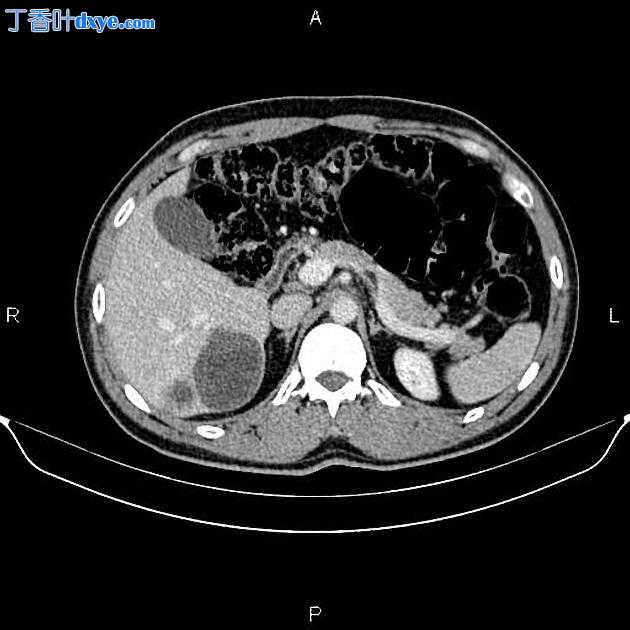

CT

Axial non-contrast

在右肝叶小于 55 mm 处可见三个相邻的厚壁囊性病变。

此外,还描绘了一个直径为 15 毫米的低密度肝病灶,位于第 4 肝段(Couinaud 的命名法),显示早期外周、结节状强化和向心性充盈。特征与血管瘤最相容。